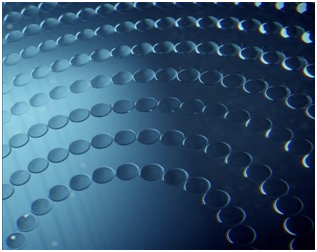

Линзы при близорукости от компании Stellest являются самым современным и эффективным методом коррекции детской миопии. В таких линзах используется технология H.A.L.T. – кольцо высокоасферических микролинз, которые замедляют рост глаза и нормализуют работу аккомодационного аппарата.

Линзы ZEISS MyoCare

В линзах при близорукости ZEISS MyoCare используются специальные микроструктуры в периферической зоне линзы. Центральная часть, предназначенная для коррекции зрения вдаль, окружена практически невидимыми кольцами, которые обеспечивают коррекцию зрения. Такая методика предотвращает быстрое удлинение глаза и замедляет прогрессирование миопии.